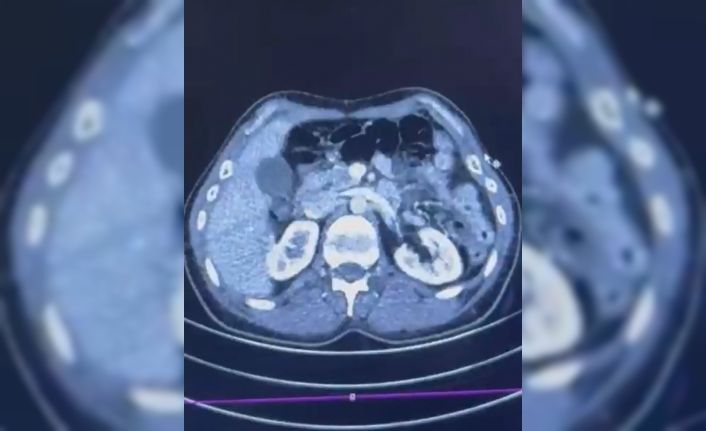

Edinilen bilgiye göre Narkotik Suçlarla Mücadele Şube Müdürlüğü ekiplerince uluslararası uyuşturucu madde ticareti yapan kurye şahıslara yönelik gerçekleştirilen çalışmalarda, İran’dan Türkiye’ye uyuşturucu madde getirdiği tespit edilen şüpheli şahısların yakalanması amacıyla operasyon düzenlendi. Düzenlenen operasyonda; S.C., R.B.C. ve G.M. yakalandı. S.C. ve R.B.C.’nin Kayseri Şehir Hastanesi’nde yapılan iç beden muayenelerinde, mide kısımlarında bulunduğu tespit edilen 50 adet kapsül şeklinde toplam 554 gram uyuşturucu madde ele geçirildi. Şüpheliler gözaltına alınarak haklarında ’Uyuşturucu Madde Ticareti Yapmak’ işlem başlatıldı.